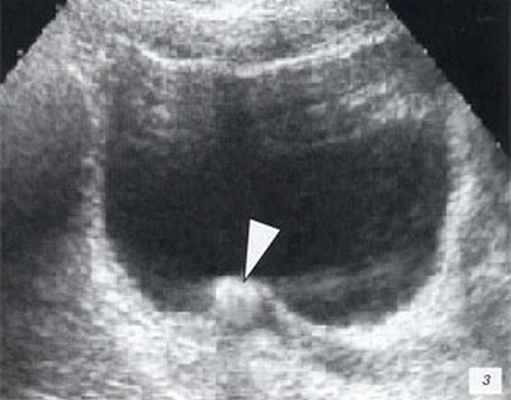

Мочекаменная болезнь, конкремент в лоханке почки.

Конкремент в устье мочеточника

3. УЗИ при уриноме:

• Гипоэхогенное скопление жидкости с тонкими стенками в околопочечном пространстве, забрюшинном пространстве или в тазу:

о Можно обнаружить несколько тонких перегородок

о Повышенная сложность (толстые перегородки/стенки, прилежащий детрит/внутреннее эхо) может указывать на суперинфекцию